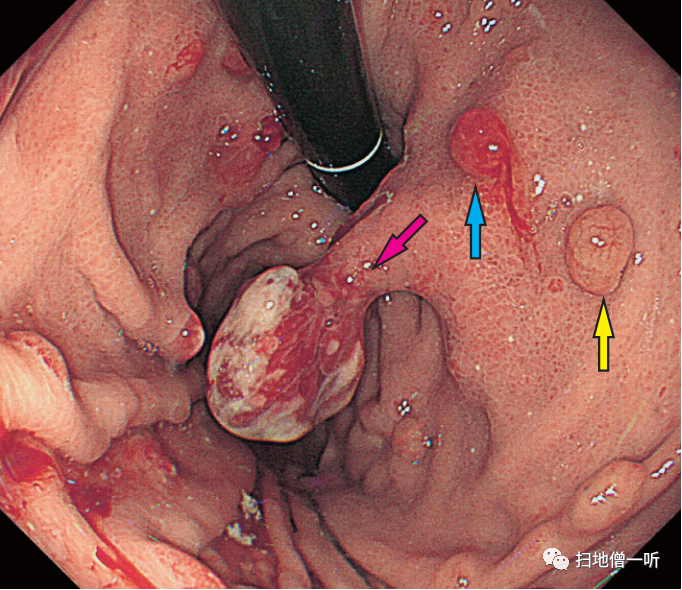

患者70多岁,女性。血清抗H.pylori抗体效价(E―plate)为阴性(不足3U/ml)。贲门部的增生性息肉的大小为5mm(红色箭头)。

▼使用PPI/P―CAB 2年后,增大到30mm。附近的红肿息肉也显示了增大的倾向(蓝色箭头),正色调的胃底腺息肉(黄色箭头)没有大的变化。

▼将P―CAB变更为PPI后,在第2周的内镜检查中确认了息肉的缩小。

因使用PPI而发现胃增生性息肉增大的病例。通过投用PPI/P―CAB,贲门部的增生性息肉显著增大,使用Bonoprazan 20mg时,血清胃泌素值为2820 pg/ml,显示出显著的高值。将Bonoprazan变更为雷贝拉唑后,变更后2周内镜检查发现息肉缩小,血清胃泌素值降低到970pg/ml。在病理组织学上,在增生性息肉中发现了小凹上皮的显著增生性变化,但没有异型性。在附近的胃底腺息肉中,在组织学上发现了PCP样所见。